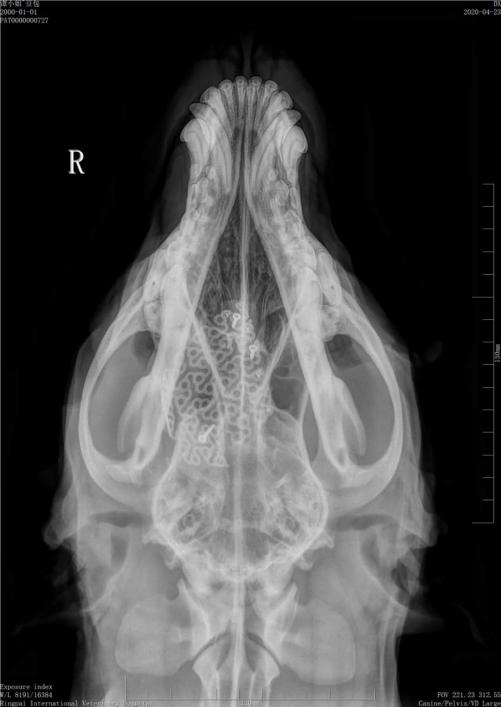

术后影像

术后患宠恢复顺利,修复后的头颅天衣无缝,外观对称良好,原来伴发的临床症状也随之缓解,于近日康复出院。